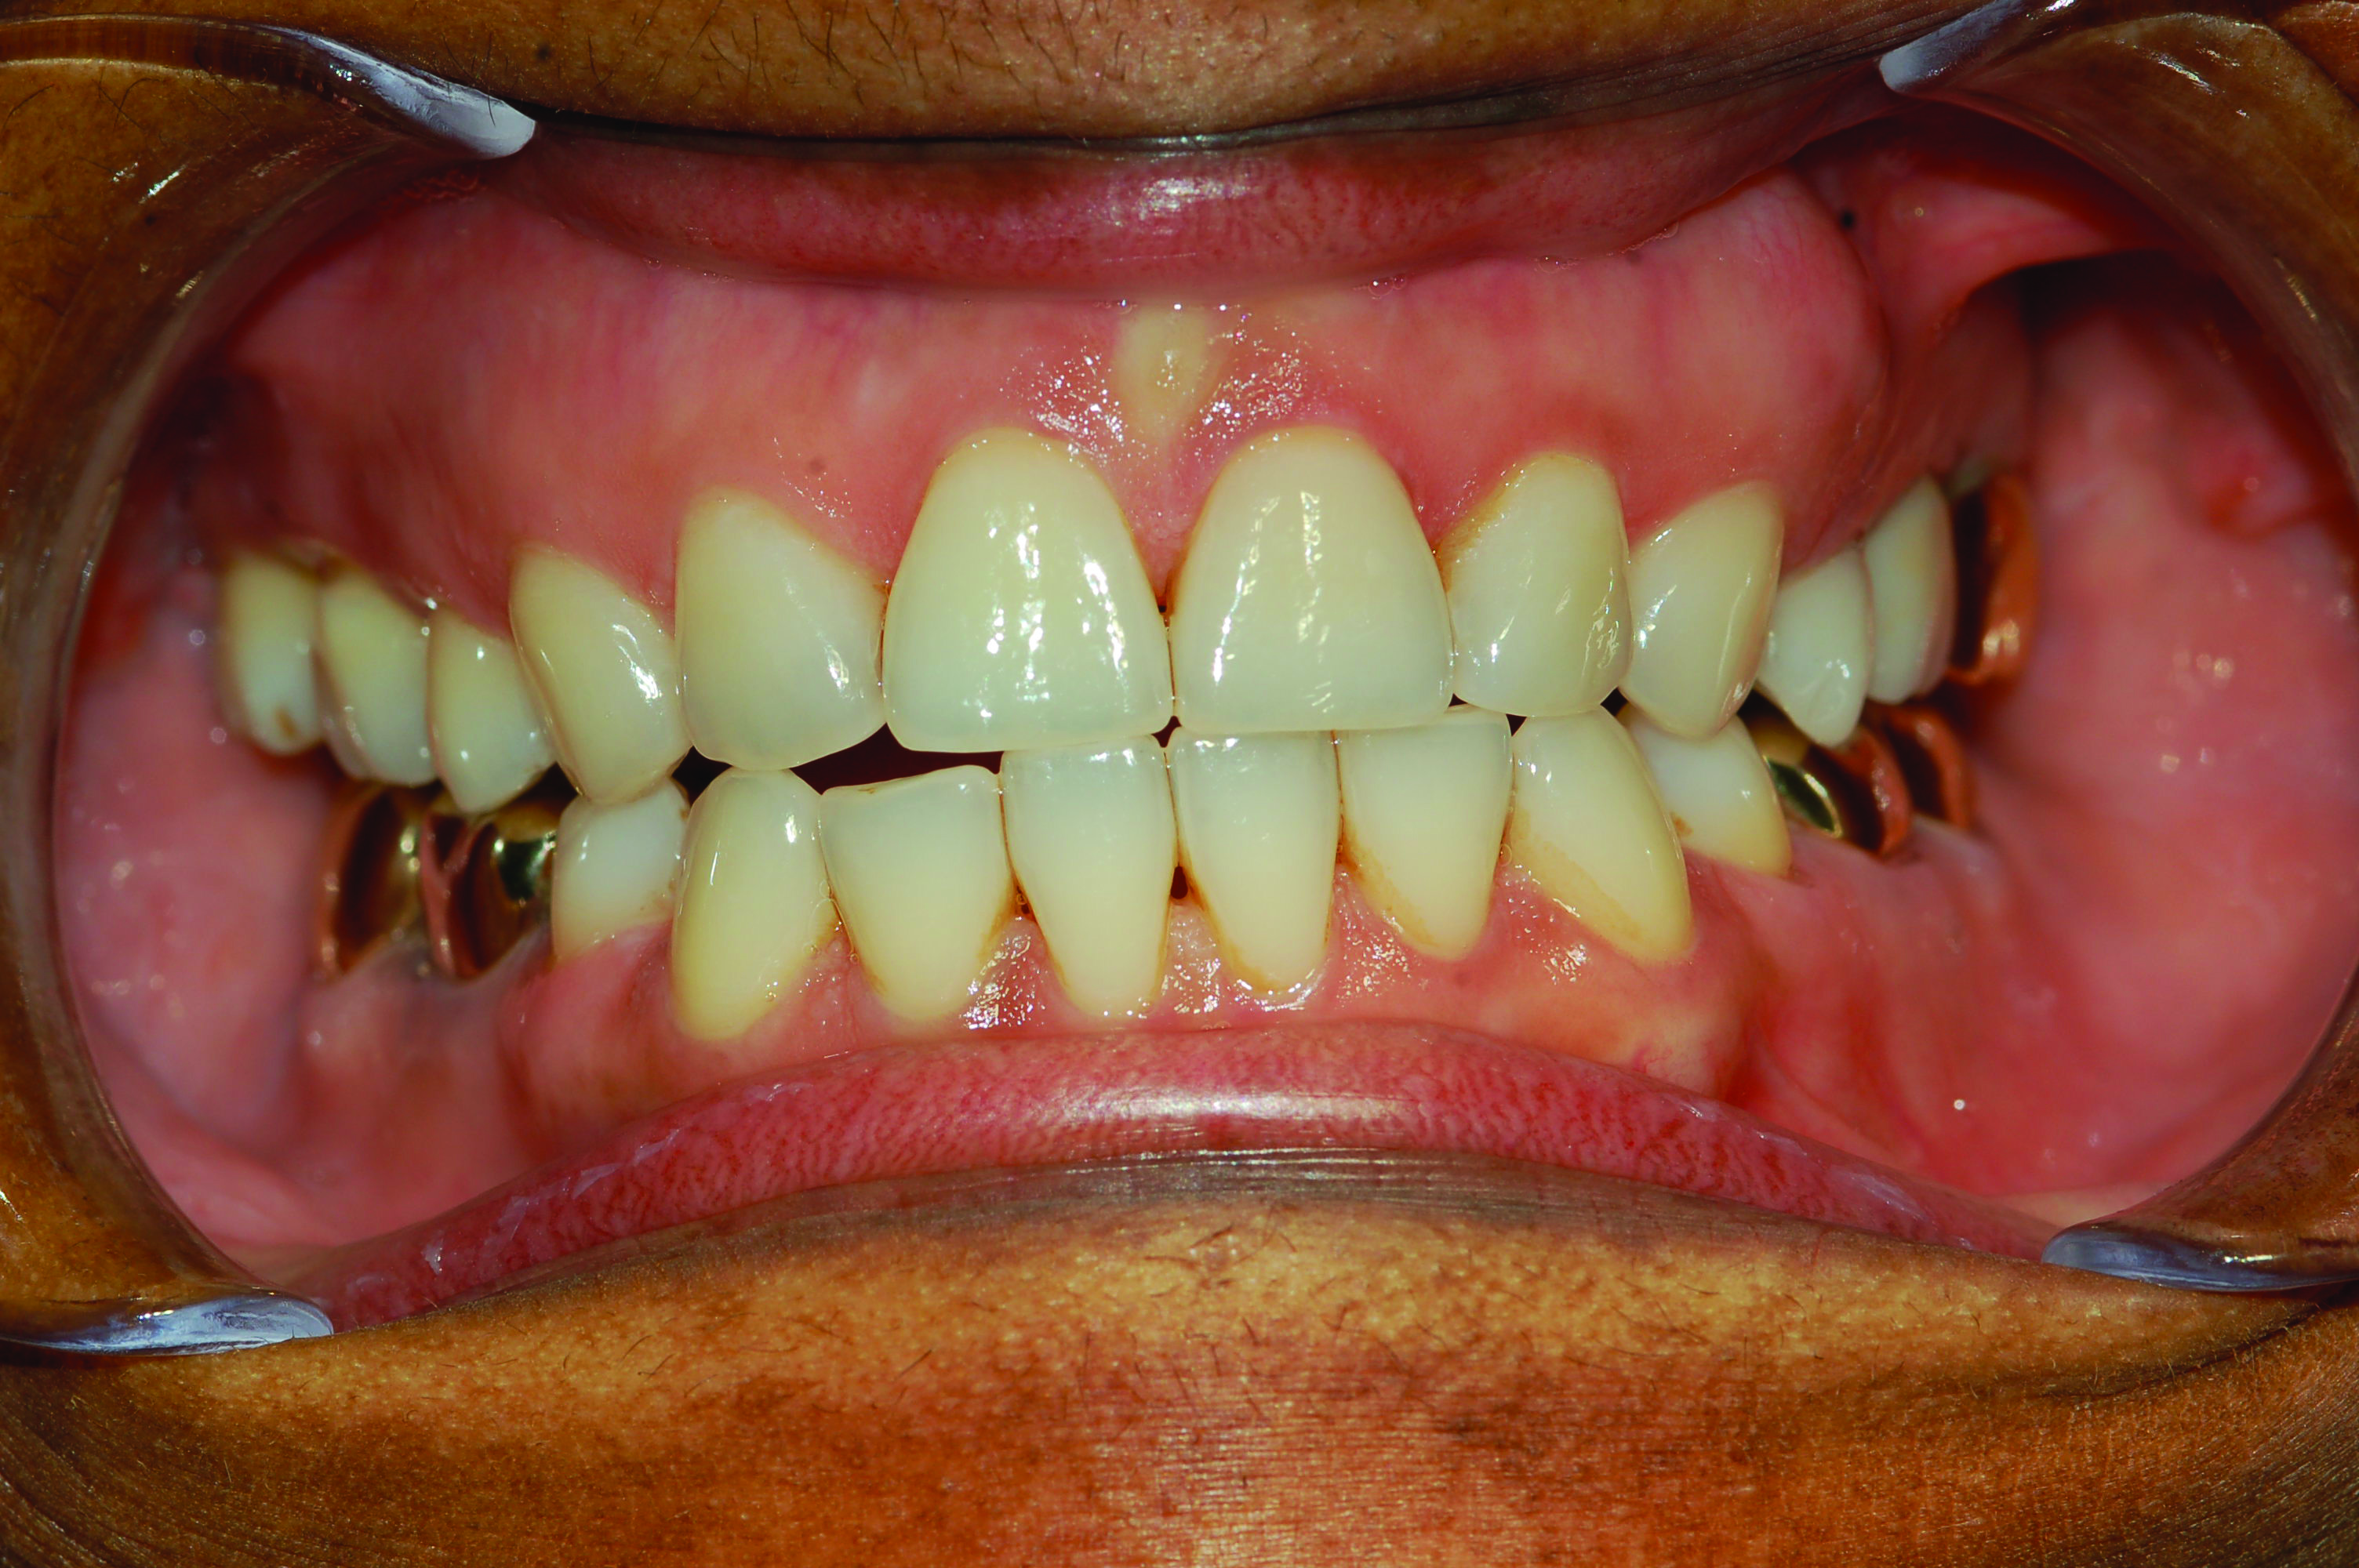

Fig 7. Development of posterior open bite. Photograph of male patient with teeth maximally intercuspated prior to treatment (AHI in supine position = 88.2 events/hr).

Figure 7

Fig 8. Photograph of teeth maximally intercuspated 10 months after patient began treatment with a MAD (TAP® appliance). With the jaw advanced 95% of maximum protrusion, the AHI in the supine position was reduced to 1.1 events/hr. A posterior open bite was observed on both sides of the dental arch.

Figure 8